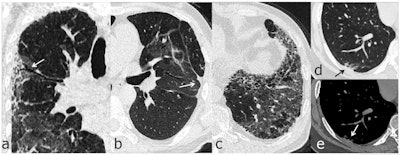

Chest follow-up CT findings of COVID-19 pneumonia: (a) traction bronchiectasis; (b) parenchymal bands; (c) honeycombing; (d, e) thickening of adjacent pleura. Images and caption courtesy of the RSNA.The investigators found that 35% of the study participants (40 of 114) went on to develop lung changes within six months. Patients with the following factors at disease onset were at higher risk of manifesting signs of lung damage at six-month follow-up: